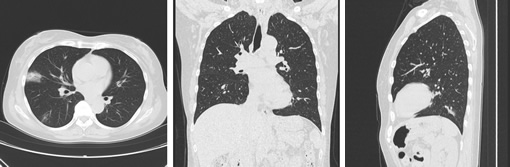

画像例(胸部)

- 120kv 210mAs/scan time 11sec